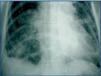

Se trata de una paciente mujer de 54 años con antecedentes de hipertensión e insuficiencia renal crónica no filiada en programa de diálisis peritoneal desde hacía 8 meses, que fue ingresada en nuestro servicio por diarrea con hipotensión y un episodio de rectorragia. El examen físico abdominal fue irrelevante. Los hallazgos analíticos mostraron hiperamilasemia cerca de 900 U/l (42-220 U/l) con leucocitosis de 22,1 X 109 l. Los demás parámetros de laboratorio estaban en rango de la normalidad. Se analizó el líquido peritoneal descartando peritonitis. La radiografía simple abdomen (figura 1) mostró opacificaciones difusas en colon que correspondían a los comprimidos de carbonato de lantano introducidos 2 meses antes del ingreso como tratamiento de la hiperfosfatemia (0,75 g oral 3/día). Se practicaron dos colonoscopias sin éxito que informaban de pobre preparación y un stop en la progresión del colonoscopio. En una tomografía computarizada abdominal se detectó la presencia de un fecaloma impactado en el área rectosigmoidal. No se evidenciaron masas patológicas pancreáticas ni en el resto del abdomen. El fecaloma pudo ser extraído y el mismo día la paciente presentó disnea brusca y empeoramiento del estado general con hipotensión y desaturación de oxígeno. En la radiografía simple de tórax (figura 2) se observaron líneas radioopacas siguiendo los alvéolos pulmonares. Se reinterrogó a la familia confirmando la administración de los comprimidos de Lantano suspendidos en el ingreso. La paciente fue hemodializada sin mejoría del cuadro pulmonar y falleció.

Figura 2.